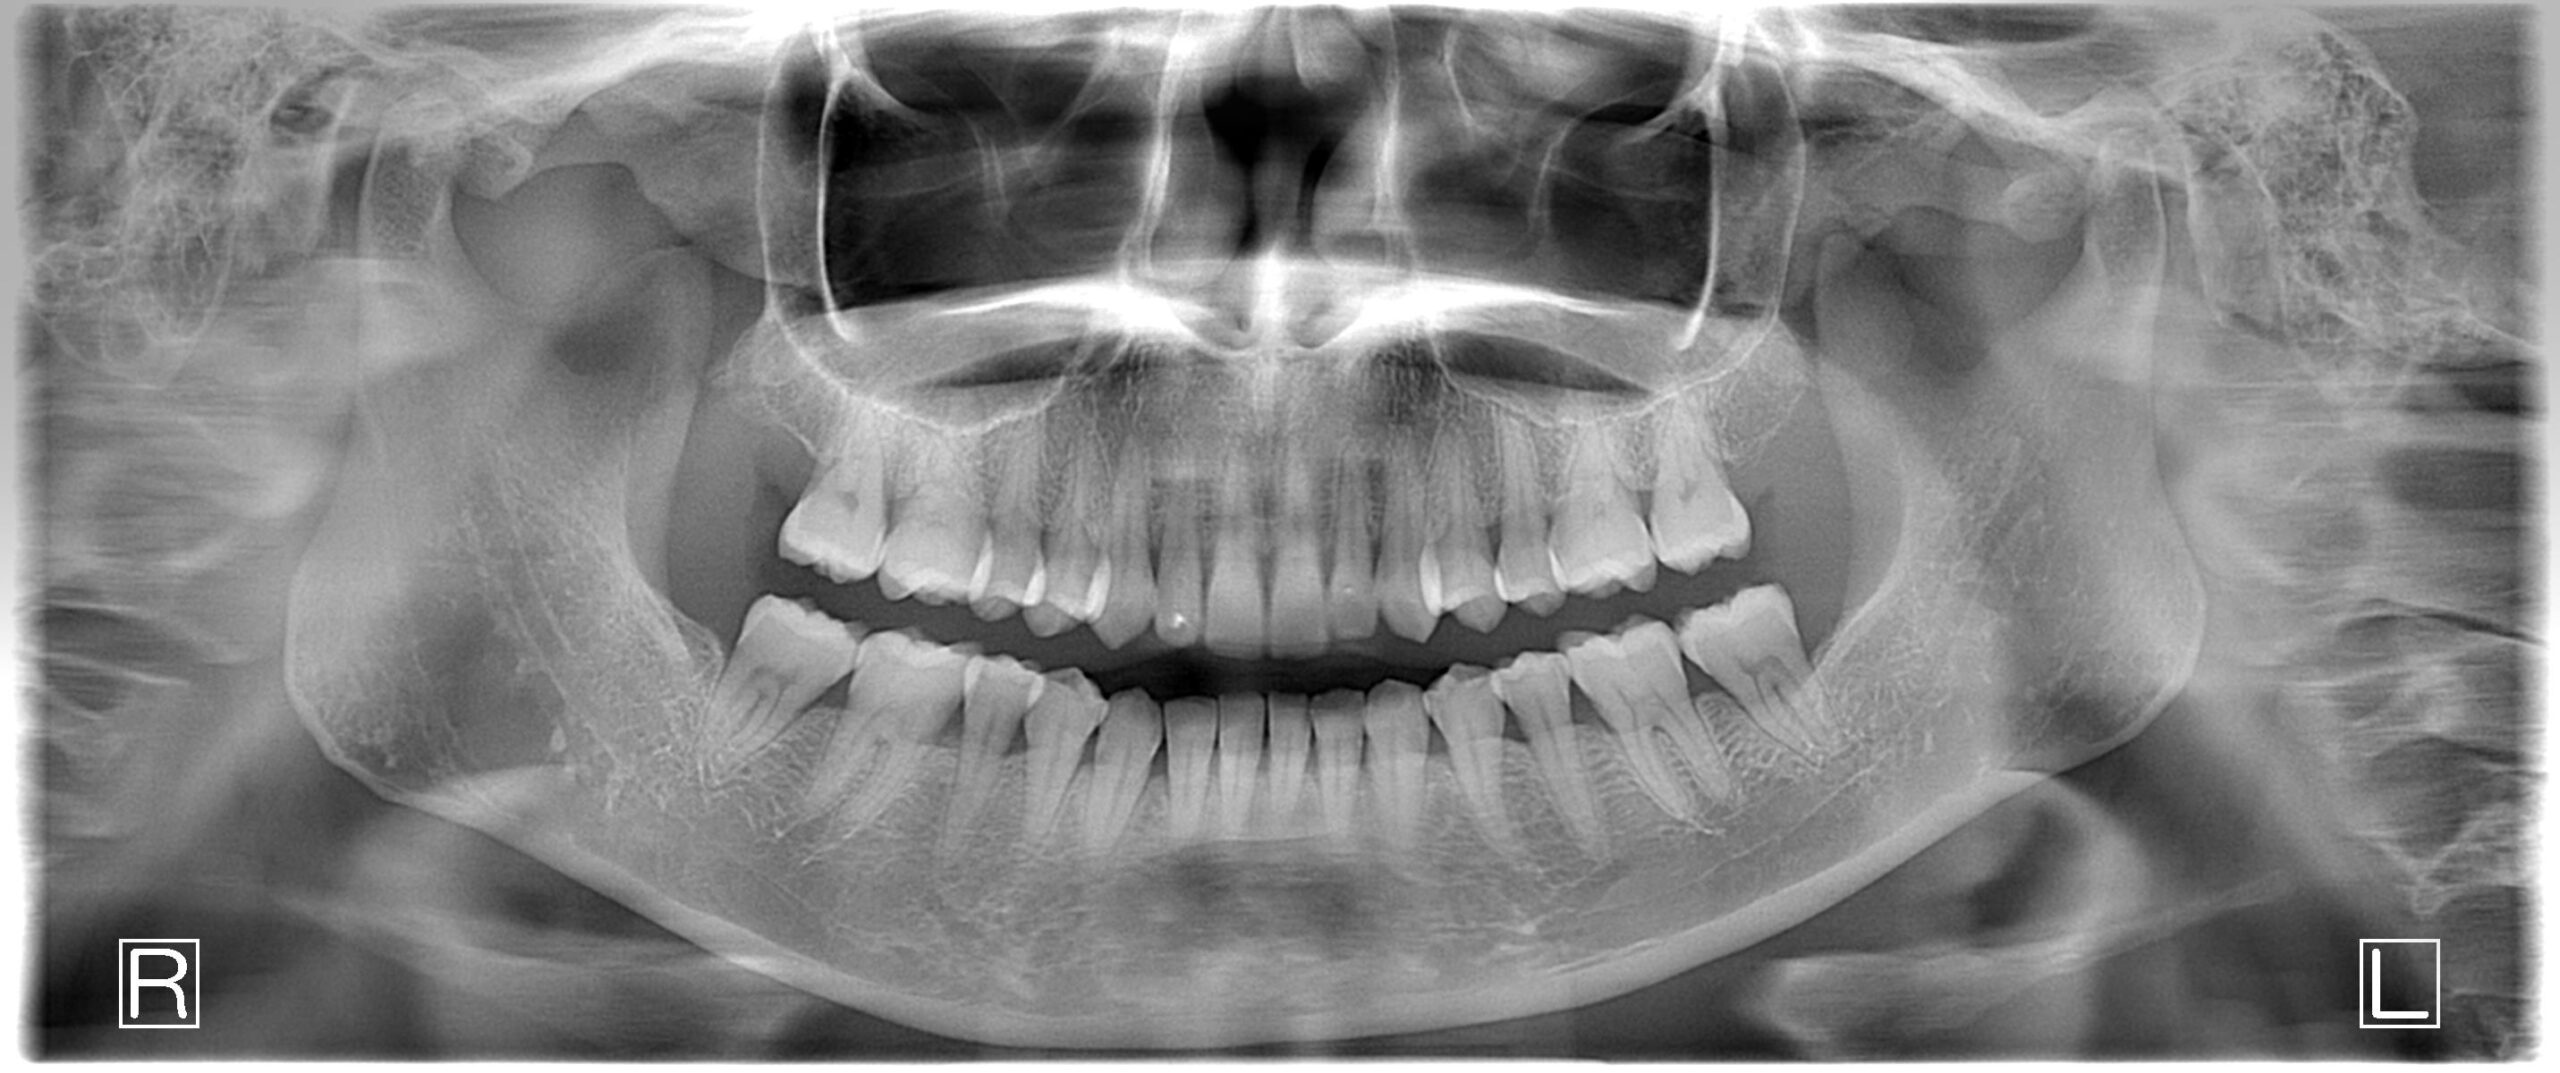

After